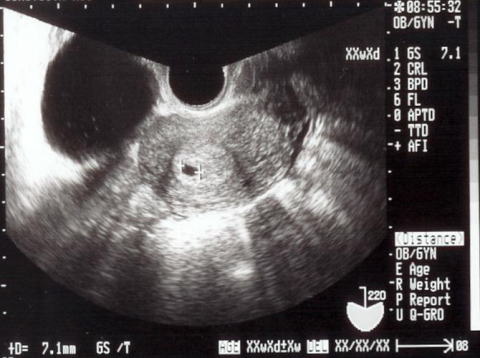

5週2日

shigeruは無事でした!

左下の黒くなっているところが袋で、shigeruは真ん中の白い影(見えるかな)だよ。袋が17ミリしかないから、まだまだ米粒だね。